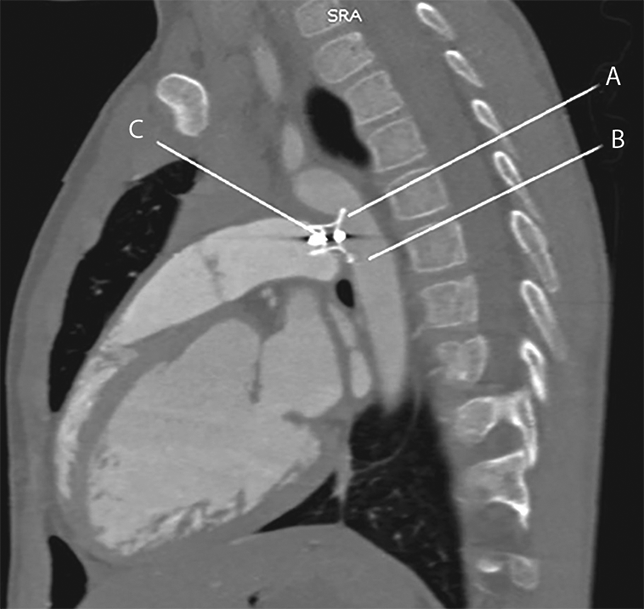

Представлен клинический случай стентирования перешейка аорты с целью устранения редкого осложнения — стеноза, вызванного окклюдером, который был имплантирован в открытый артериальный проток ребенку в возрасте 7 мес. Через 7 лет пациент повторно поступил в кардиологический центр с клиникой коарктации аорты, по данным эхокардиографии выявили пиковый градиент давления в зоне имплантации окклюдера 40 мм рт. ст., градиент давления между верхними и нижними конечностями 25–30 мм рт. ст. В возрасте 8 лет компрометацию кровотока в аорте полностью устранили стентированием перешейка аорты с армированием имплантированного окклюдера открытого артериального протока. Имплантировали стент Andrastent XL (Andramed GmbH, Ройтлинген, Германия), который можно раскрыть до 14 мм. При контрольной тензиометрии градиент давления на перешейке аорты полностью устранен. Через 7 мес. эффективность вмешательства подтвердили данными эхокардиографии. Тактика стентирования аорты устройством с потенциалом расширения по мере роста ребенка является обоснованной в силу эффективности, малоинвазивности и радикальности.